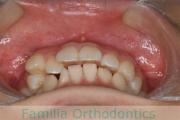

No.22V-104

- 側方偏位

- 叢生

- 19歳

- 女性

- FEA

- 90万円

歯並びを綺麗にしたいということで来院されました。叢生(でこぼこ、凹凸、ガタガタ)と上下顎前突のため、上下左右から小臼歯を抜歯の上で、歯科矯正用アンカースクリューを併用したマルチブラケット法を行いました。約2年半、30回の通院が必要でした。

上下とも叢生がありますので、後戻りのリスクがあります。